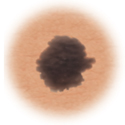

Color. El lunar tiene distintos colores. Puede ser tostado, marrón, negro, rojo o de otros colores. O puede tener zonas que parece que se decoloraron.

Melanoma |